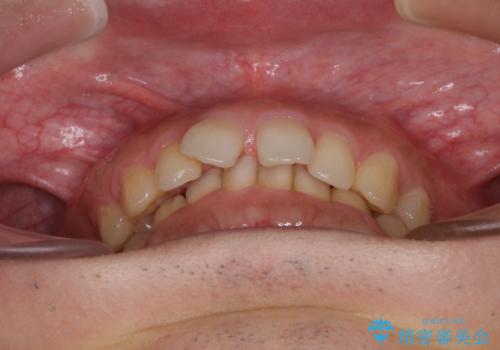

- 前歯の隙間を気にして来院された患者様です。

下顎前歯が見えなくなるくらいに深い咬み合わせであり、さらに上顎の正中が開くほど下の前歯が突き上げている状態でした。

奥歯は手前に倒れてしまっているため、後方に起き上がらせることで深い咬み合わせ・ディープバイトを改善する必要があります。

ディープバイトの方は項合力が強大であることが特徴のため、仕上がりを重要視して、ワイヤー装置にて矯正治療を行うこととしました。